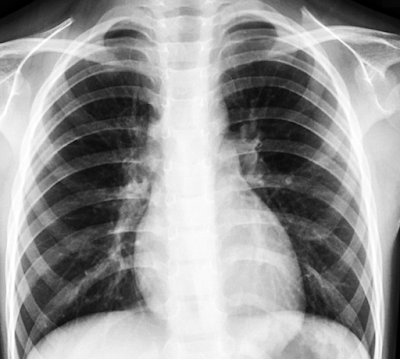

[Quick x-ray tutorial: The lungs show dark because they contain air. Pnemonia shows up as white. This severe level of pneumonia could put a patient on the ventilator.]

Normal chest x-ray (Case courtesy of Bruno Di Muzio, Radiopaedia.org)